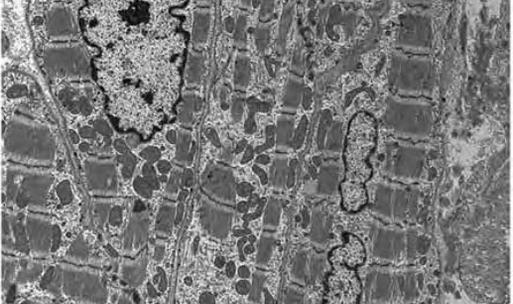

- 7 细胞膜的超微结构与超微病变

- 8 细胞核的超微结构与超微病变

- 9 内质网的超微结构与超微病理

- 10 高尔基复合体、线粒体的超微结构与超微病变

- 11 溶酶体和微体的超微结构与超微病变

- 12 细胞骨架、中心粒、纤毛、鞭毛、包含物的超微结构与超微病变

- 13 细胞超微结构与超微病理观察(实验)

- 14 心血管系统的超微结构与超微病变